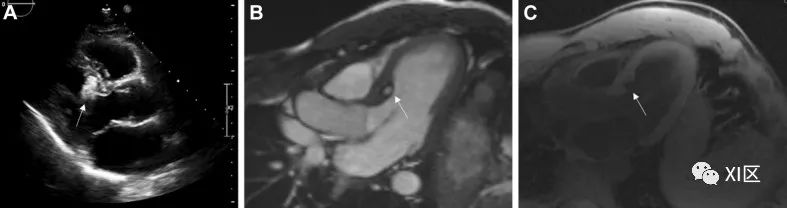

平滑肌肉瘤 平滑肌肉瘤(图 8)很罕见,但具有高度侵袭性。通常只有在肿瘤发展到晚期时才会出现症状。完全切除和辅助化疗或放疗可略微改善预后。

图 8 心旁平滑肌肉瘤因胸痛就诊的 42 岁男性,心包旁平滑肌肉瘤。(A)心旁肿块(白色箭头)紧邻左室心尖,在 CMR 的 SSFP 成像中,该肿块似乎位于心包外部,但与心包紧密粘连。(B)CMR 显示心包旁肿块(白色箭头)无后期钆增强。(C)CMR 脂肪-水抑制成像信号强度增高。

平滑肌肉瘤占所有心脏肉瘤的 8%-9%,是一种罕见且侵袭性极强的心脏肉瘤,文献报道不超过 200 例。这些肿瘤通常出现在左心房后部,表现为无梗肿块,外观呈粘液状。这种肿瘤也见于所有其他心腔。组织学上,肿瘤由紧密的纺锤形细胞束组成,细胞核钝化并有坏死区域,有丝分裂像和上皮样区域经常出现。

临床表现取决于肿瘤的位置和大小,但在晚期之前通常没有症状。浸润心肌的肿瘤常伴有心律失常。其他不太常见的表现包括静脉和主动脉内血栓形成。在心脏 CT 上,平滑肌肉瘤表现为不规则的分叶状低度肿块,并伴有心包积液。它们通常侵犯二尖瓣和肺静脉,表现为充盈缺损。也可能出现萎缩性钙化。